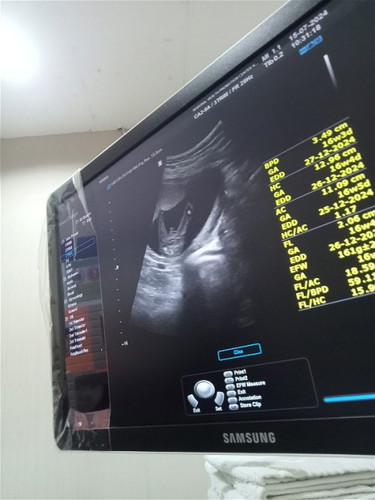

ตอนท้องคนแรกเป็นผู้ชายไม่มีอาการแพ้อะไรเลยกินอร่อยนอนหลับเต็มอิ่มและท้องแหลม พอท้องสองแม่แพ้ท้องมากและท้องกลมใครๆเห็นก็ว่าผู้หญิงเเน่ๆแม่ก็นึกว่าจะได้ผู้หญิงตามที่คิดไว้ เเต่พอไปซาวหมอบอกเป็นผู้ชายตามรูปจ้า แม่มีหวังที่จะมีน้องสาวให้พี่ชายมั้ยน้าา😂 มีใครตอนไปซาวด์ว่าเป็นผู้ชายเเต่พอออกมาเป็นผู้หญิงไหมคะ ตอนนี้16w

เหมือนกันเลยจ้า การเพ้การกินแตกต่างกันมากมีแต่คนทักว่าผู้หญิง วันนี้หมอซาวด์ดู ทั้งจู๋ทั้งไข่มาเต็มเลย แอบผิดหวังนิดๆ #ท้อง1-2 ก็ผู้ชาย อยากได้หญิงสักคนหมดหวังเลย🥹🥹🥹

อยากได้ลูกสาวสักคนเหมือนกันค่ะแม่ แต่โชว์ให้เห็นชัดมากเลย

โชว์ขนาดนี้ผช.เเน่นอน100%ค่ะตอนท้องเเม่ก็ชัดเเบบนี้ในใจคงจะมีเปอร์เซนบางว่าต้องเป็นผญ.บ้างพอคลอดมาผช.จ้า